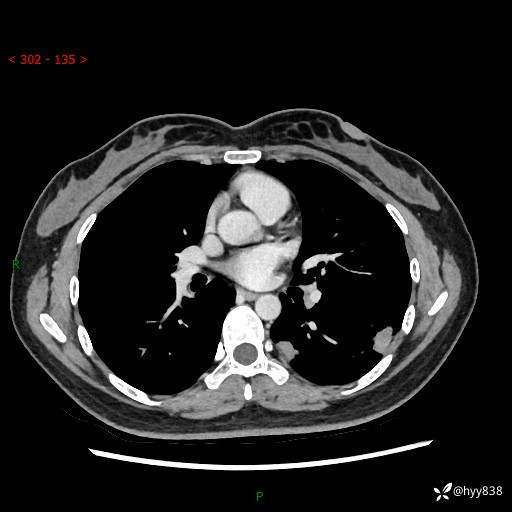

【患者信息】:36岁/女

【主诉】:左侧下胸部阵发性疼痛2周,乏力1周

【现病史及既往史】:患者自诉2周前饮酒后出现左侧下胸部阵发性疼痛,不随呼吸改变,无咳嗽咳痰、头晕头痛、咳血、呼吸困难等不适,于当地第一人民医院查胸部CT提示肺部感染,随后前往我院门诊给予抗感染(左氧氟沙星)治疗1周,自诉胸痛较前好转,感乏力、头晕,偶尔干咳,无咳痰,无发热、畏寒、胸闷、咯血、四肢酸痛、腹泻、腹痛等不适,门诊复查胸部CT提示:左肺下叶感染,病灶较前增加增大,遂以“肺部感染”收入我科。 起病以来,患者精神、饮食、睡眠可,大小便正常,体力体重无明显变化。

【检查】:胸部CT增强(外院平扫)